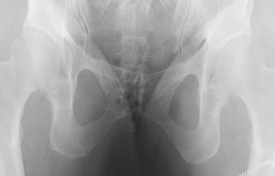

Gonadal shields should be used on pelvis and hip procedures for all male children and adults of childbearing age. Contact shields should be placed over the testes with the upper edge of the shield placed at the inferior margin of the symphysis pubis.

For AP and “frog-leg” laterals of the hips, specially shaped ovarian shields can be carefully placed over the area of the ovaries without obscuring essential anatomy as shown. This should be done on all female children and adults of childbearing age. These ovarian shields, however, may obscure essential anatomy on certain pelvic examinations. Departmental policy regarding shielding and kV range to be used should be determined.

• Supine, pelvis centered to CR and to IR; use gonadal shields on both male and female. (Use ovarian shield of appropriate size for female, ensuring that it does not cover hip areas.)